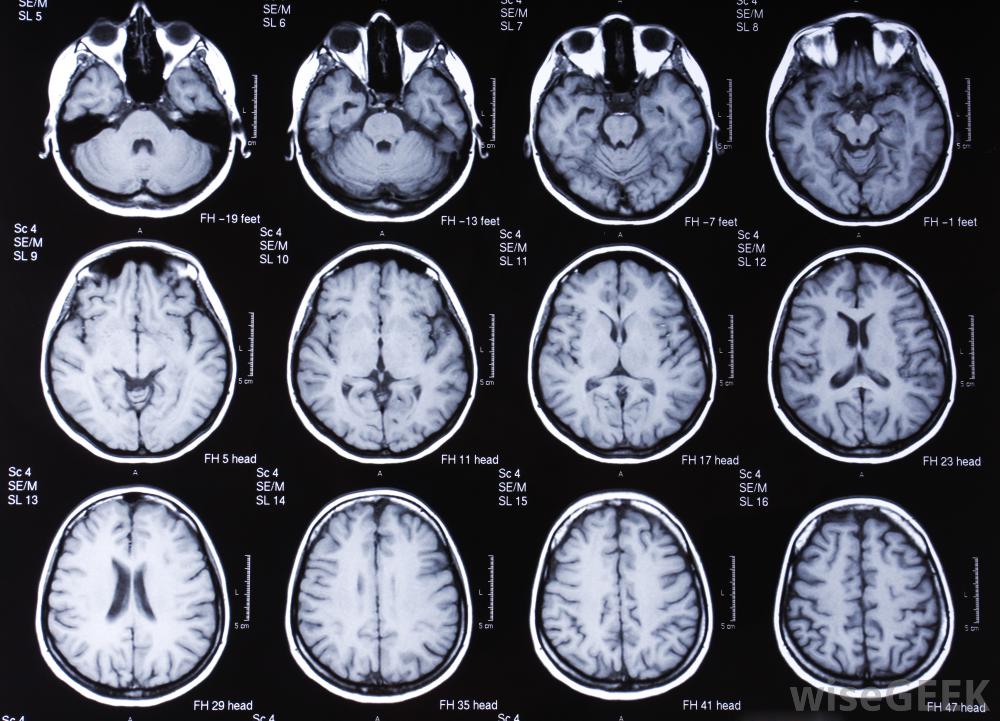

腦部的核磁共振掃描。

腦MRIs對研究者和醫生都很重要。